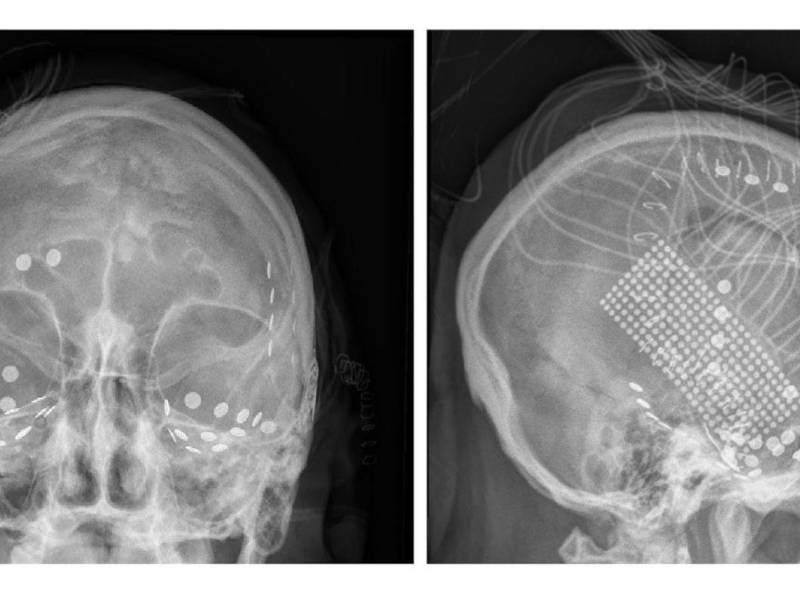

Electrodos registraron señales del cerebro de pacientes con epilepsia mientras escuchaban “Another Brick in the Wall”.

Recrean una canción del cerebro

Al comprender mejor cómo el cerebro metaboliza la música, los científicos esperan construir nuevas “prótesis del habla”.